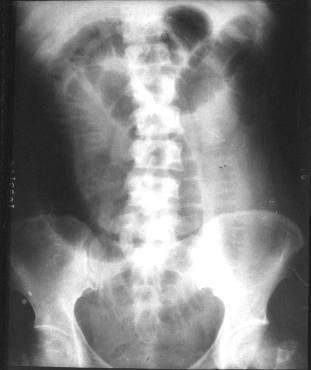

Bk72t.jpg

(311 × 370像素,文件大小:11 KB,MIME类型:

肠梗阻